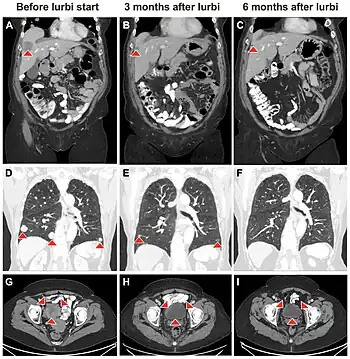

- ↑ Moussa, Mohammad Jad; Khandelwal, Jaanki; Wilson, Nathaniel R.; Naik, Sagar A.; Subbiah, Vivek; Campbell, Matthew T.; Msaouel, Pavlos; Singh, Parminder; Alhalabi, Omar (13 June 2024). "Durable Objective Response to Lurbinectedin in Small Cell Bladder Cancer with TP53 Mutation: A Molecular-Directed Strategy". Current Oncology. 31 (6): 3342–3349. doi:10.3390/curroncol31060254. ISSN 1718-7729. Retrieved 26 January 2025.